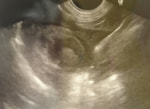

胆嚢の超音波検査所見

超音波検査所見

胆嚢粘液嚢腫エコー